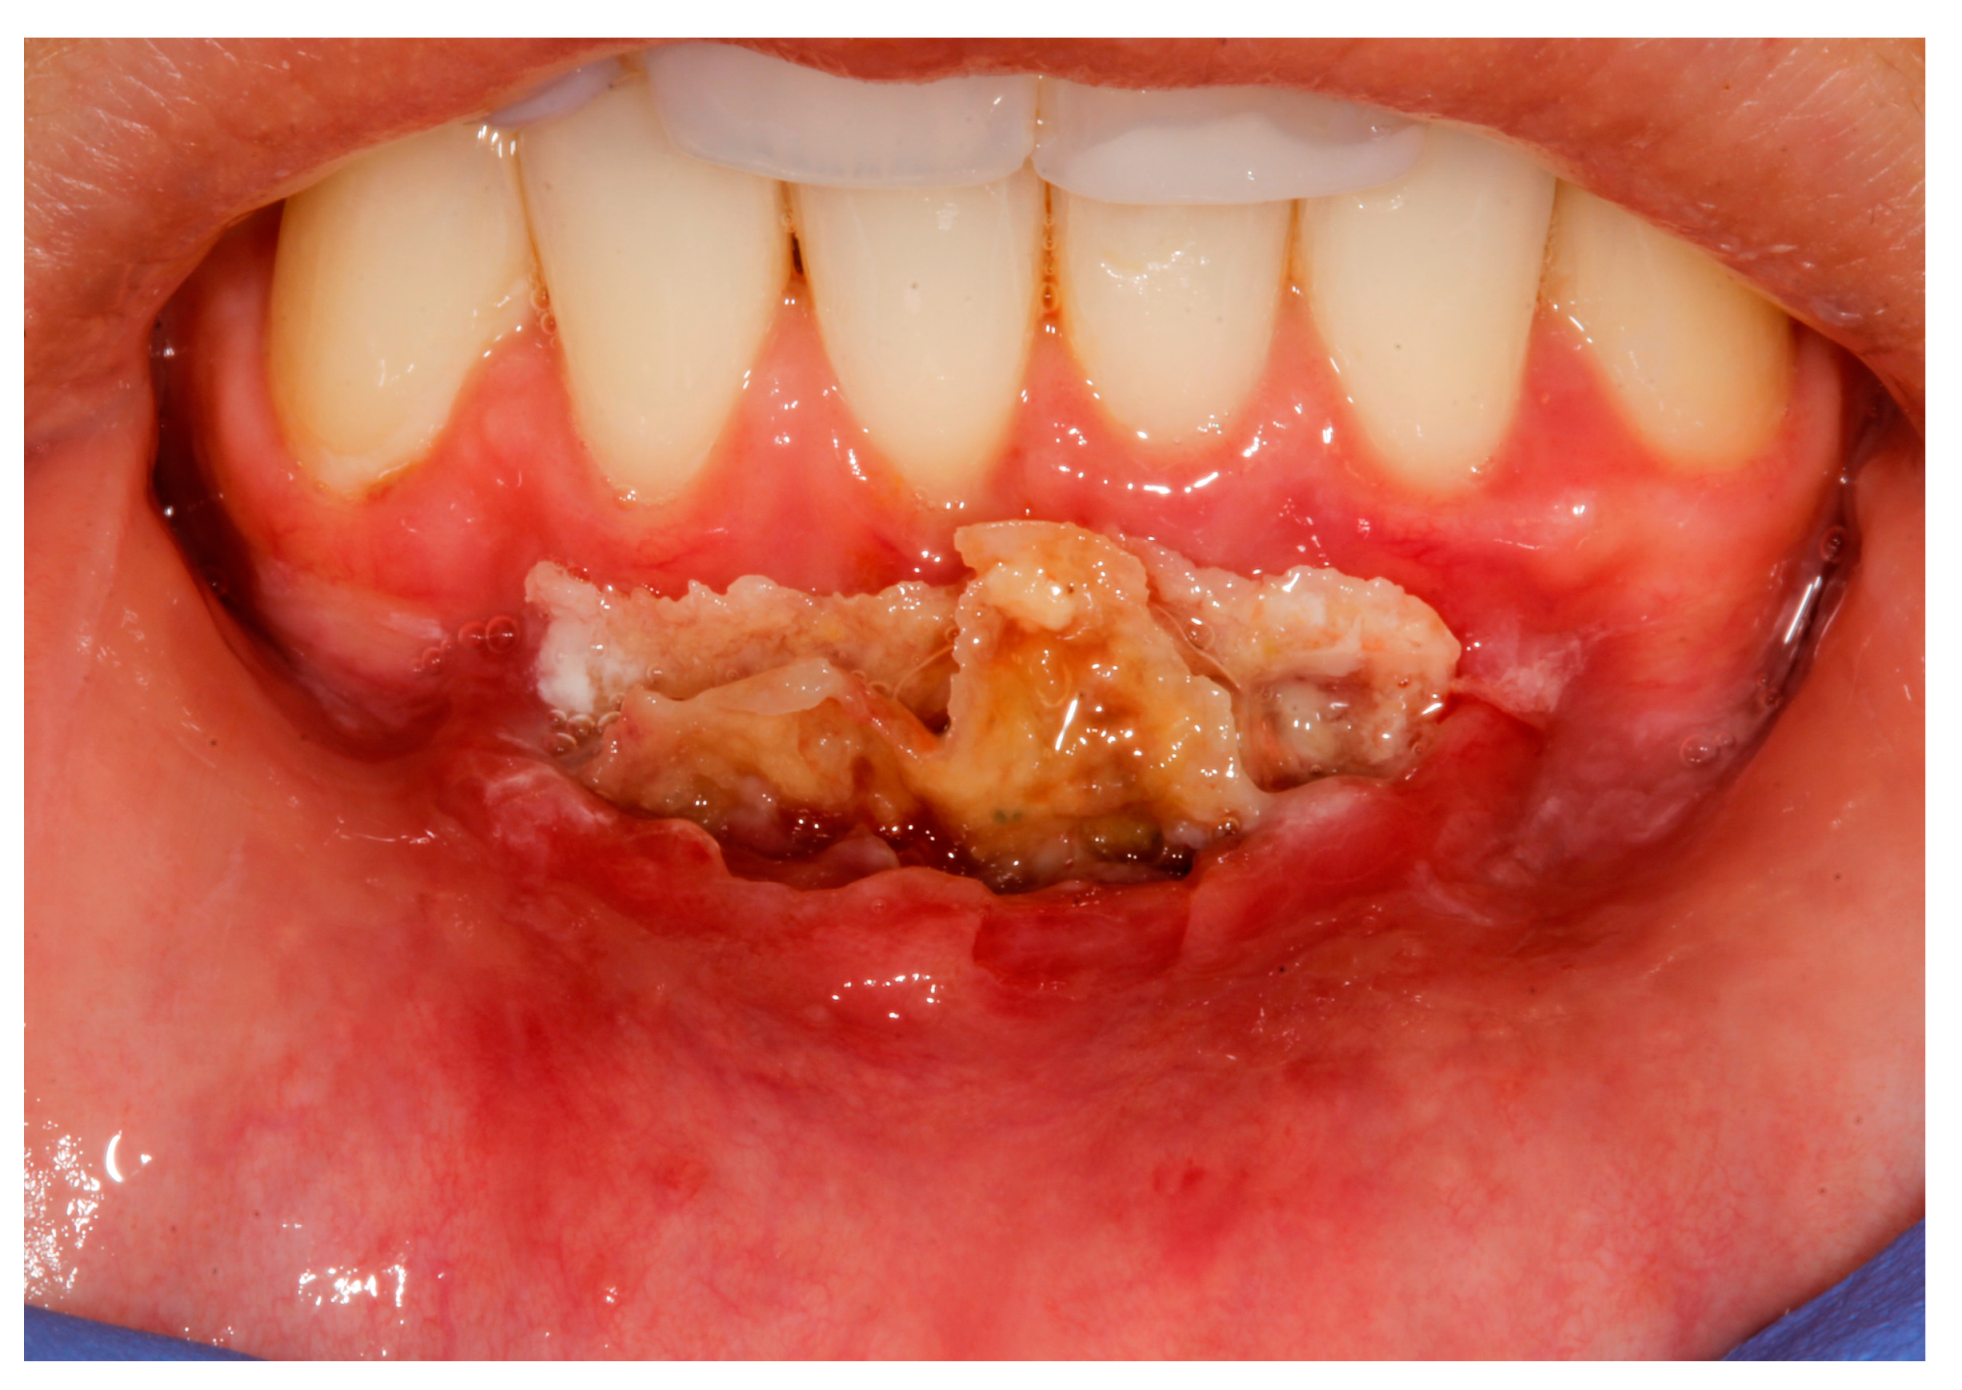

2. Case Study

- (a)

- deep partial thickness incision (blade parallel to the periosteum) made at the level of the external insertion of the frenulum;

- (b)

- elimination of superficial mucous tissue and muscle of the frenulum;

- (c)

- a series of detached points with periosteal anchorage for the apical positioning of the lining mucosa of the lip and the second intention healing of the exposed periosteum.